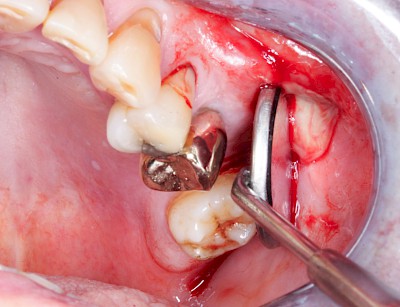

Schwellung mit Eiter: Abszess

Schwellungen im Zusammenhang mit akuten Entzündungen im Bereich der Zähne oder dem Zahnhalteapparat entstehen meist aufgrund schneller und starker Vermehrung von Bakterien sowie einer starken Abwehrreaktion des Körpers (Abszess). Diese Schwellungen entstehen meist in sehr kurzer Zeit – innerhalb von Stunden oder wenigen Tagen. Die Schwellungen sind sehr schmerzhaft. Nah am Zahnfleisch kann sich bei leichtem Druck auf die Schwellung Eiter entleeren. Mitunter fühlen sich die Menschen krank. In fortgeschrittenem Stadium kann auch Fieber auftreten. Hier ist sofort der Zahnarzt zu kontaktieren, um eine weitere Ausbreitung der Entzündung zu verhindern.